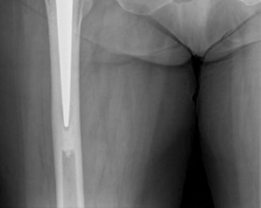

Femoral Preparation and Cementing Technique

Attention was then turned to the femur. The proximal femur was elevated and externally rotated. The femoral canal was entered using a box osteotome, taking care to lateralize the entry point into the greater trochanter to avoid varus malpositioning of the stem.

The canal was sequentially broached using a collarless, polished, double-tapered stem system. In a cemented technique, the broach size determines the size of the cement mantle, not the press-fit of the stem. A line-to-line broaching technique was used to allow for a uniform 2mm cement mantle.

7. Stem Insertion: The polished, double-tapered stem was inserted in the correct version (approximately 10-15 degrees of anteversion) and held rigidly until the cement fully polymerized.